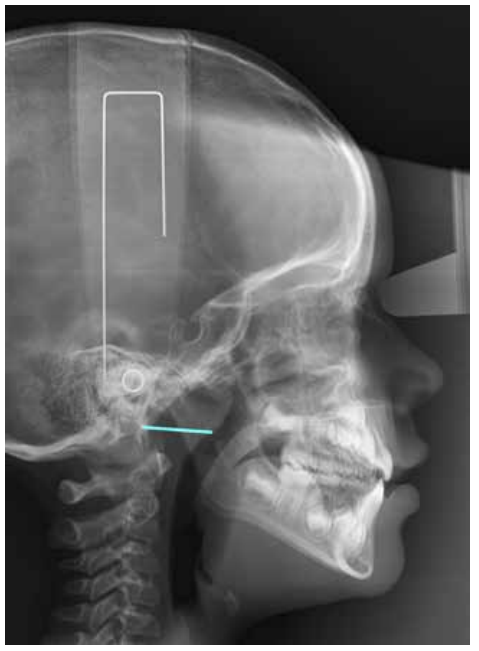

Finally, the distance was measured between the intersection point of the posterior pharyngeal wall and the line formed between the posterior nasal spine along with the basion (Ad1-Ba), refer to Figure 3.